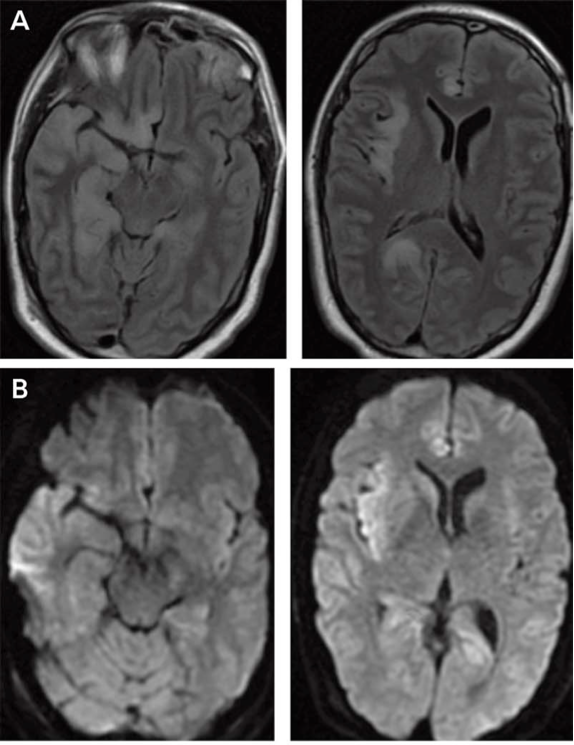

RMN: Edema temporal o frontal, involucro bilateral temporal casi patognomónico